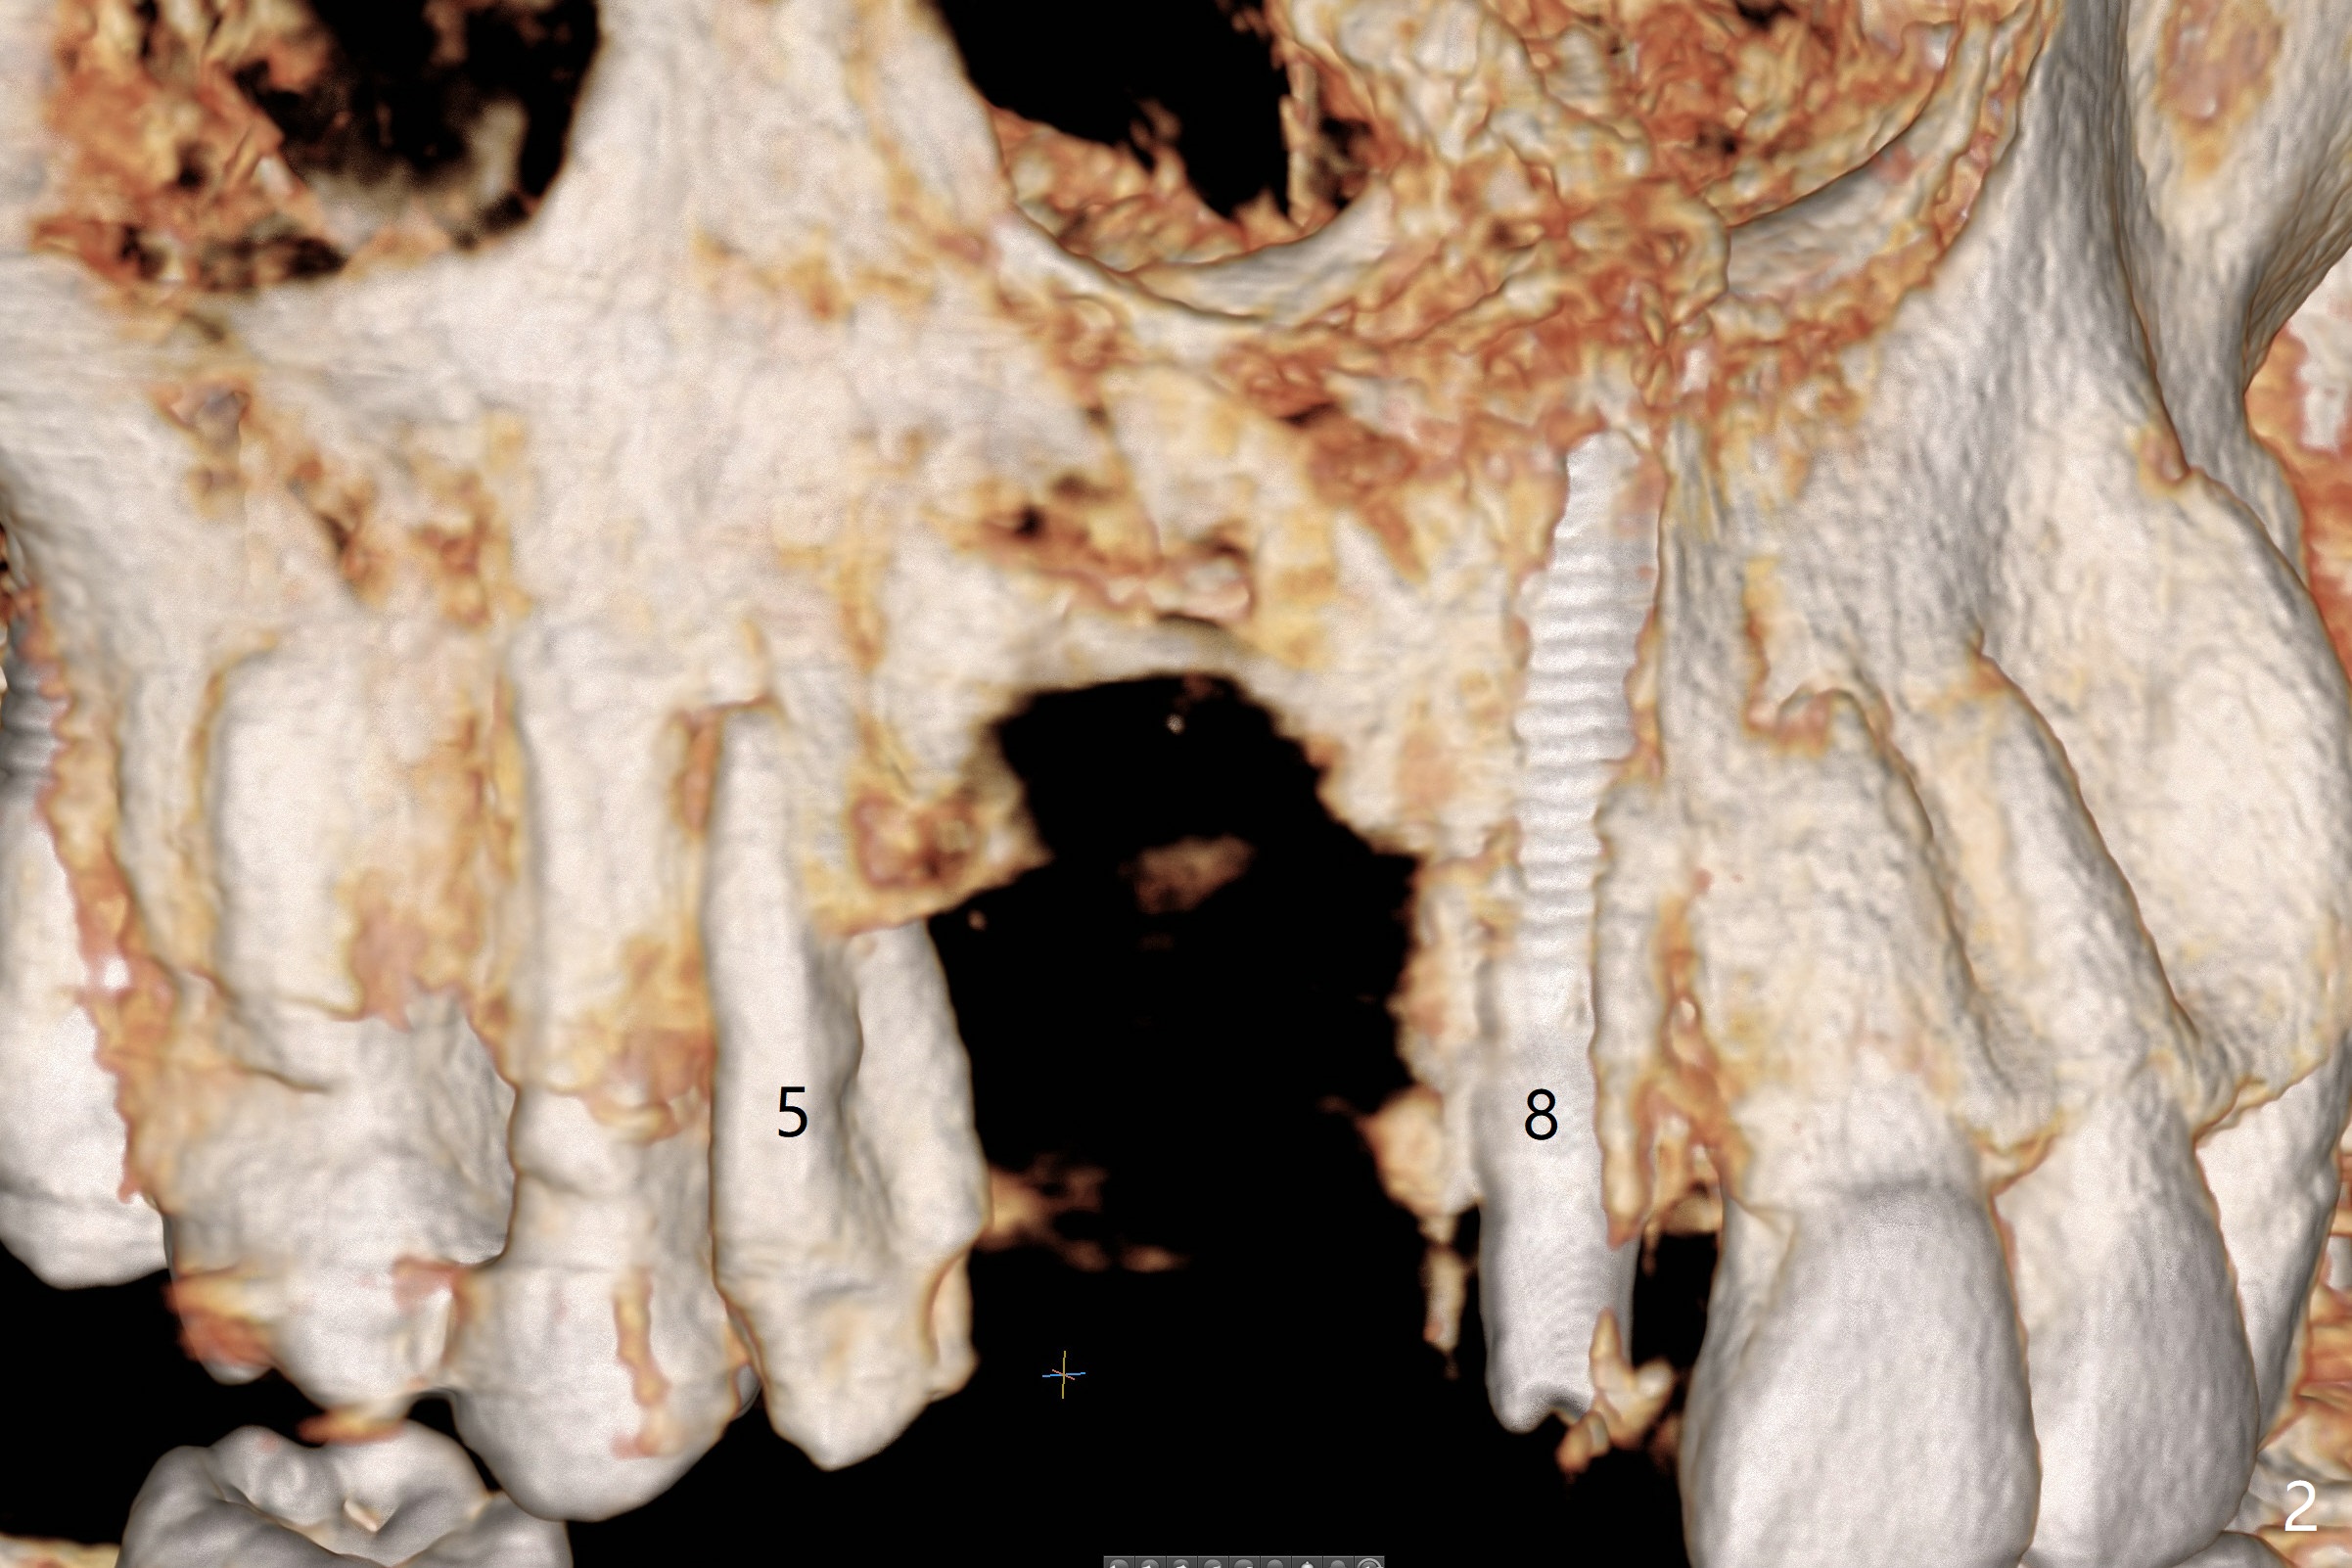

A 51-year-old woman lost the teeth #6 and 7 due to odontoma removal ~30 years ago. The area was restored with a FPD. The latter is removed with immediate implant at #8 8-9 months earlier. Particulate bone graft does not repair the bone deficiency at #6, 7 (Fig.2,3), although the soft tissue looks bulky (Fig.1). It appears that the palatal defect also needs a piece of bone block to fill in (Fig.4). The block will be harvested from the chin (Fig.5,6). If the block graft turns out to be impracticable, the periodontally compromised tooth #5 (bone loss, Fig.2,3,7) will be extracted for immediate implant. Initial osteotomy will be established in the palatal socket (Fig.8,9). Either a 2- (Fig.10) or 1- (Fig.11) piece implant will be placed. After wound healing, impression will be taken for a lab-fabricated provisional FPD.